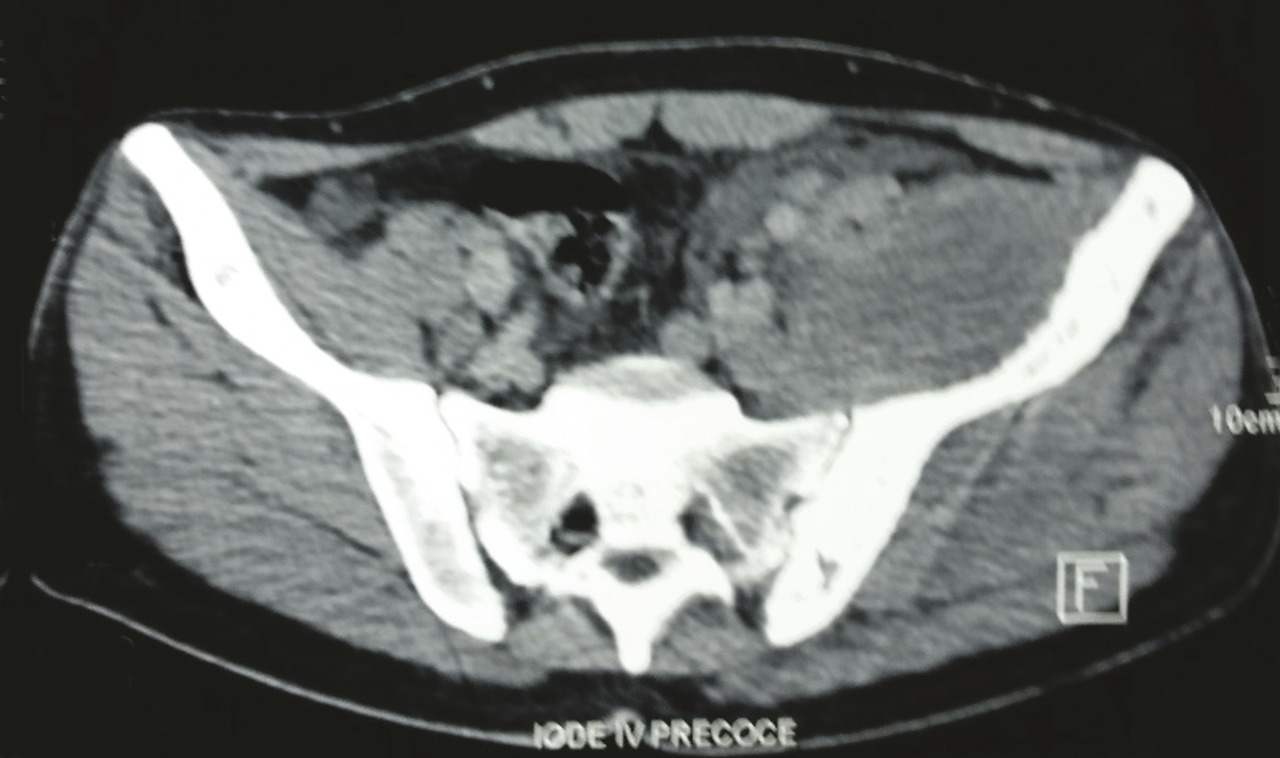

Les radiographies standards mettent en évidence une vertèbre ivoire L1 ainsi qu’une ostéocondensation de l’os iliaque gauche (fig. 1 ). Le scanner thoraco-abdomino-pelvien montre une atteinte osseuse mixte de l’aile iliaque gauche (fig. 2 ), un envahissement des parties molles (avec augmentation des volumes des muscles fessiers et du psoas [fig. 3 ] expliquant la sciatalgie), une néphromégalie unilatérale, une splénomégalie nodulaire et de multiples adénopathies abdomino-pelviennes et thoraciques.

Sur les clichés conventionnels, on décrit trois types de lésion : lytique (la plus fréquente avec 50 à 80 % des cas)2, condensante et mixte. L’ostéocondensation isolée est rare (5 % des cas).9 Elle peut réaliser l’aspect classique de la vertèbre ivoire qui est plus fréquemment rencontré dans le lymphome de Hodgkin que dans les lymphomes non hodgkiniens.2 L’association d’une lésion osseuse et d’une importante infiltration des tissus mous en regard alors que la corticale est conservée ou finement mitée est évocatrice du lymphome.9 Dans les cas où l’infiltration lymphomateuse est confinée à la cavité médullaire, les radiographies standards peuvent être normales. La tomographie par émission de positons est l’examen de référence pour evaluer les atteintes osseuses et extra-osseuses.

La tomodensitométrie (TDM), quant à elle, permet de déterminer le stade et l’extension du lymphome et d’assurer le suivi des patients. L’imagerie par résonance magnétique (IRM) est un examen très sensible pour l’étude de l’envahissement des parties molles et celle de l’extension dans la moelle osseuse. L’infiltration lymphomateuse apparaît en hyposignal ou sous forme de signal hétérogène en T1 et en hypersignal T2 avec prise de contraste après injection de gadolinium.